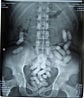

The police last week caught a woman of Asian nationality with 32 capsules of heroin hidden in her guts. “The movement of the accused was suspicious so police interrogated her on her arrival at the airport and then was taken to the ROP Hospital in Qurum,” her added.

The X-rays revealed the woman looked very uncomfortable at the airport because she had swallowed 32 capsules of heroin.